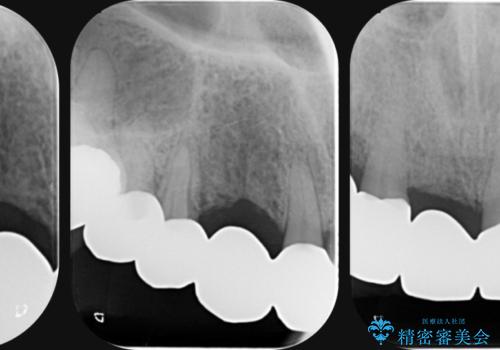

- 前歯を噛みしめにより失い、さらに犬歯もグラグラになり全く噛めなくなり改善を求めて来院されました。

過度な力がかかり周囲の骨に高度な吸収が見られた犬歯は抜歯し、機能・審美性の回復をより咬合力に対して抵抗力のあるブリッジ補綴にて対応します。

過度な咬合力は歯を失う元です。

ブリッジによる欠損補綴を行ったのち、ナイトガードを夜間装着していただき歯を守ります。